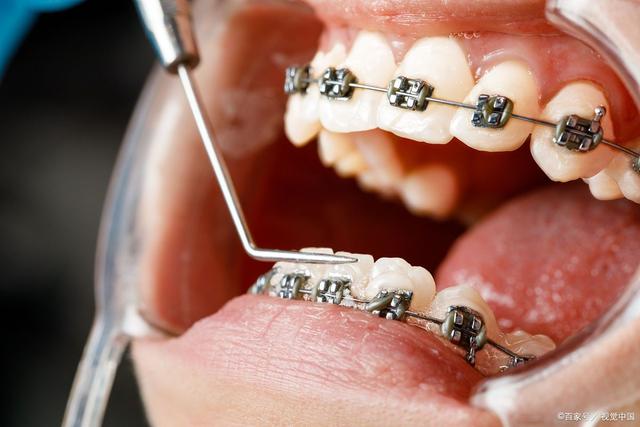

口腔正畸学可以分为传统的固定矫治和隐形矫治两种。传统的固定矫治通常使用金属托槽和附着在牙齿上的金属丝来进行矫正,而隐形矫治则是采用透明的矫治器,可以更好地满足患者的需求,并提供更加隐蔽的矫正方式。